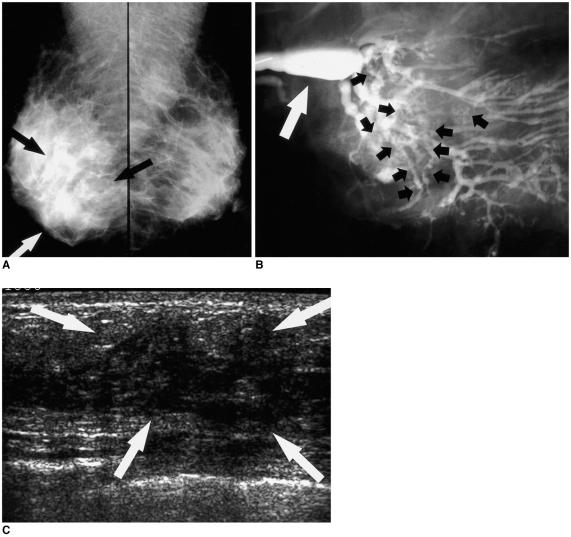

Ductographic findings of breast cancer.

Ductography has become the gold standard for the evaluation of patients exhibiting pathologic nipple discharges. In nine patients (age range, 29-67 years; median age, 51 years) with invasive (n=5) or intraductal (n=4) cancer, ductographic findings were recorded, then correlated with mammographic and sonographic findings. Common ductographic findings included complete ductal obstruction, multiple irregular filling defects in the nondilated peripheral ducts, ductal wall irregularities, periductal contrast extravasation, and ductal displacement. Faint microcalcifications or ill-defined masses, which were not opacified by contrast material, were often discovered adjacent to ductal abnormalities. Mammographically and sonographically occult diffusely spreading intraductal cancers often manifested as pathologic nipple discharge. In such cases, meticulous ductographic examinations and interpretations were crucial in order not to miss breast cancers.